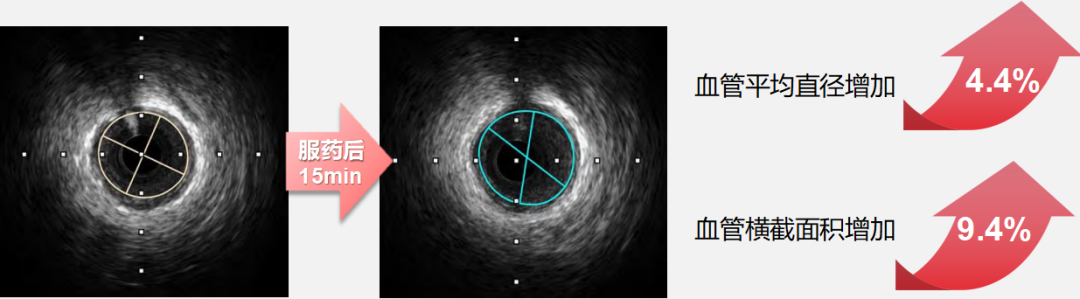

血管保护:速效救心丸精准扩张,血流更稳定

在 STEMI 院前急救中,药物对冠状动脉血管的作用不仅需实现 “扩张”,更需兼顾 “血流稳定”,避免因过度干预引发血管功能紊乱。

●硝酸甘油对冠状动脉的扩张作用呈现 “偏倚性”—— 对直径 3.00mm 以上大血管扩张效应更明显,但这种强效扩张可能伴随反射性血管收缩,且易引发血流动力学波动。在院前缺乏监护的场景中,可能增加心肌灌注不足或循环紊乱的潜在风险。

●而速效救心丸展现出 “精准化” 的血管调控特征:对直径 2.00-2.75mm 的细小冠状动脉扩张作用更突出,服药后15 分钟该直径区间血管横截面积面积扩张百分比最高可达 8.58%(如下图),且扩张过程中患者血压、心率等血流动力学指标无显著波动。

细小冠脉是心肌供血的 “最后一公里”,速效救心丸对微小血管的精准扩张作用,能有效改善心肌微循环,缓解硝酸甘油难以覆盖的微小缺血区域,同时避免大血管过度扩张引发的不良反应,这也是它在临床中缓解 “顽固性胸痛” 的重要机制之一。